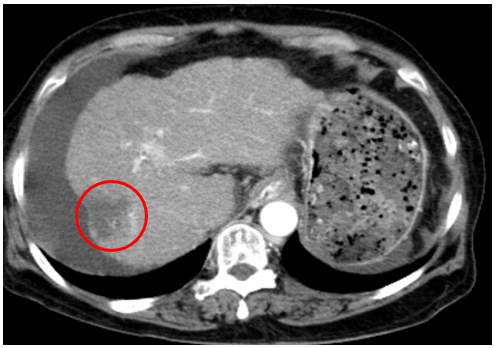

Chụp cắt lớp vi tính ổ bụng

Gan: biến đổi hình thái, phì đại HPT I, bờ gan không đều.Nhu mô gan phải có khối giảm tỉ trọng hình chêm kích thước 37x35mm, ranh giới không rõ, co kéo bao gan lân cận, trong có phần tăng tỉ trọng của vật liệu nút mạch, ngấm thuốc kém sau tiêm. Dịch quanh gan 33mm. Dịch tự do ổ bụng

=>Hình ảnh u gan phải sau điều trị hiện không thấy phần ngấm thuốc sau tiêm (Bệnh đáp ứng điều trị nên không có tổ chức ngấm thuốc) (Vòng tròn đỏ)